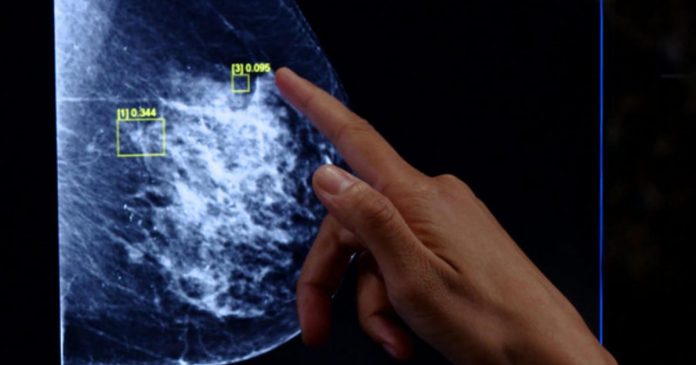

A team at Google has developed an artificial intelligence program aimed at helping doctors accurately detect cancer in mammograms. Thousands of women receive a false negative on their breast cancer tests each year, while one in 10 receive a false positive.

Shravya Shetty, who heads the Google team developing the system, told CBS News’ Jamie Yuccas that their AI model reduced false positives by almost 6% and false negatives by about 9%. Shetty also claimed that it caught suspicious tissues on mammograms missed by the human eye.

Drossman said that a computer-assisted system helps “boost accuracy” by helping draw the eye to “particular regions.”

“Mammography is very much pattern-based. There are certain patterns that we look at, either an area of speculation or calcifications, and those we know need to be biopsied. So with an AI system, it is trained to look at patterns, and the more it’s used the better it learns,” Drossman said.